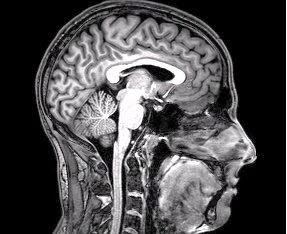

I think two of the greatest thinkers on morality and virtue, David Hume and Aristotle, can do much to help us discover some answers to these questions. Let’s explore their ideas, look for some answers there, and see how they fit with modern discoveries in behavioral science, psychology, and neuroscience.